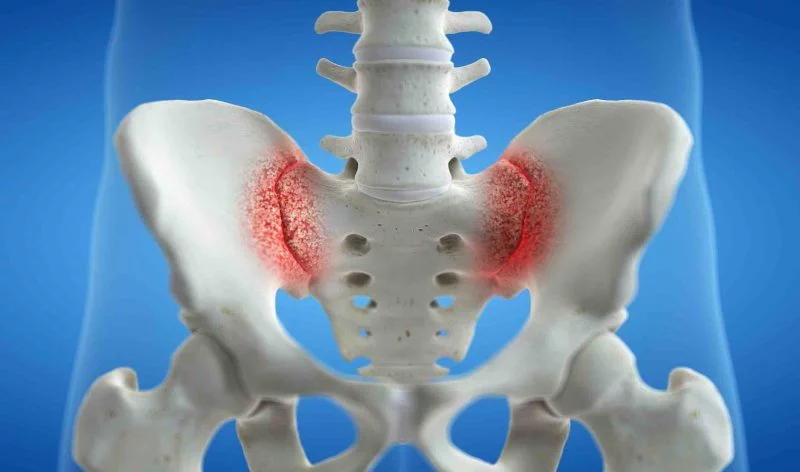

La sacroilitis o sacroileitis se refiere al dolor o inflamación de la articulación sacroilíaca, que puede afectar de forma unilateral o bilateral. Es decir afectar el lado derecho, lado izquierdo o ambos. Este dolor lumbar puede ser extremadamente debilitante y causar una disminución significativa en la calidad de vida de quienes lo padecen.

Se observa inflamación de la articulación sacroilíaca tanto derecha como izquierda